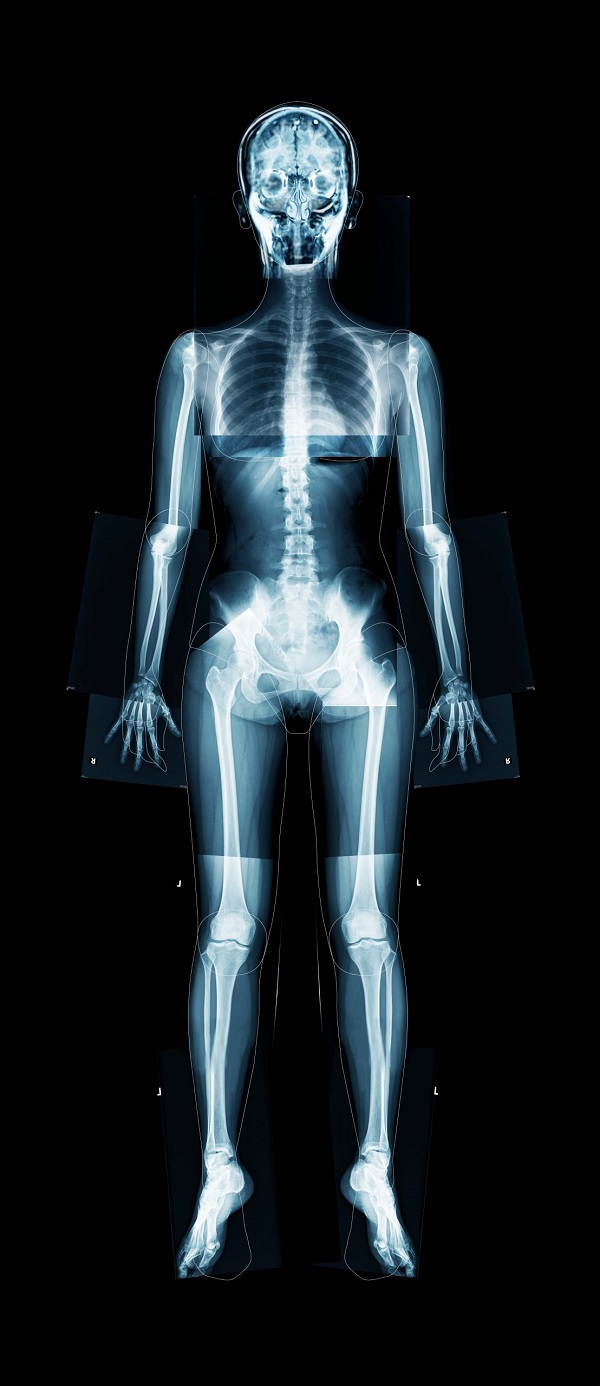

Kaguraoka’s X-ray. W45×H100×D8ライトボックス ,レントゲン